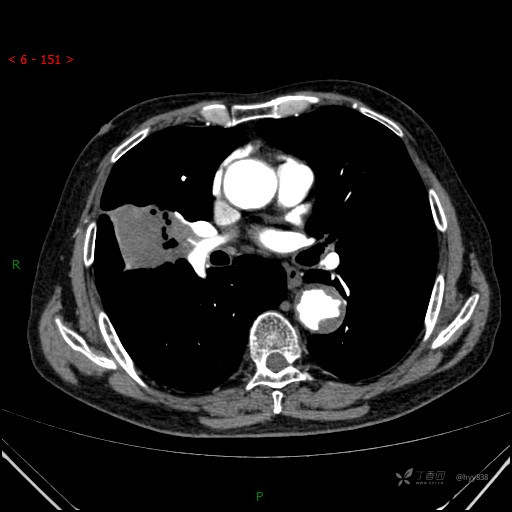

静脉期